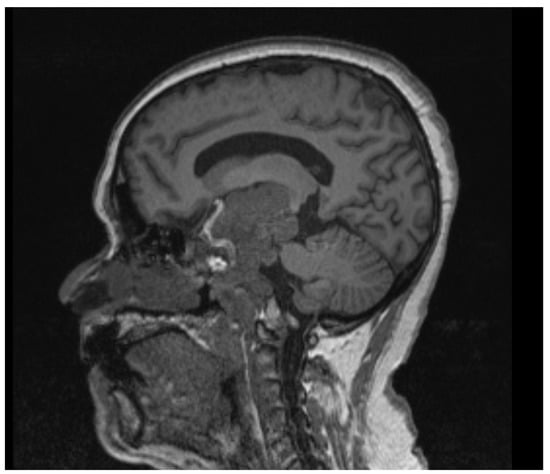

2.1. Case 1

2.2. Case 2